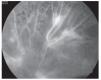

¿ Figura 2. Retinopatía diabética no proliferativa con fluorangiografía, las hemorragias son defectos en pantallas y los microaneurismas se notan como puntos brillantes.

¿ Figura 6. Fluorangiografía de retinopatía diabética con bandas fibrogliales.